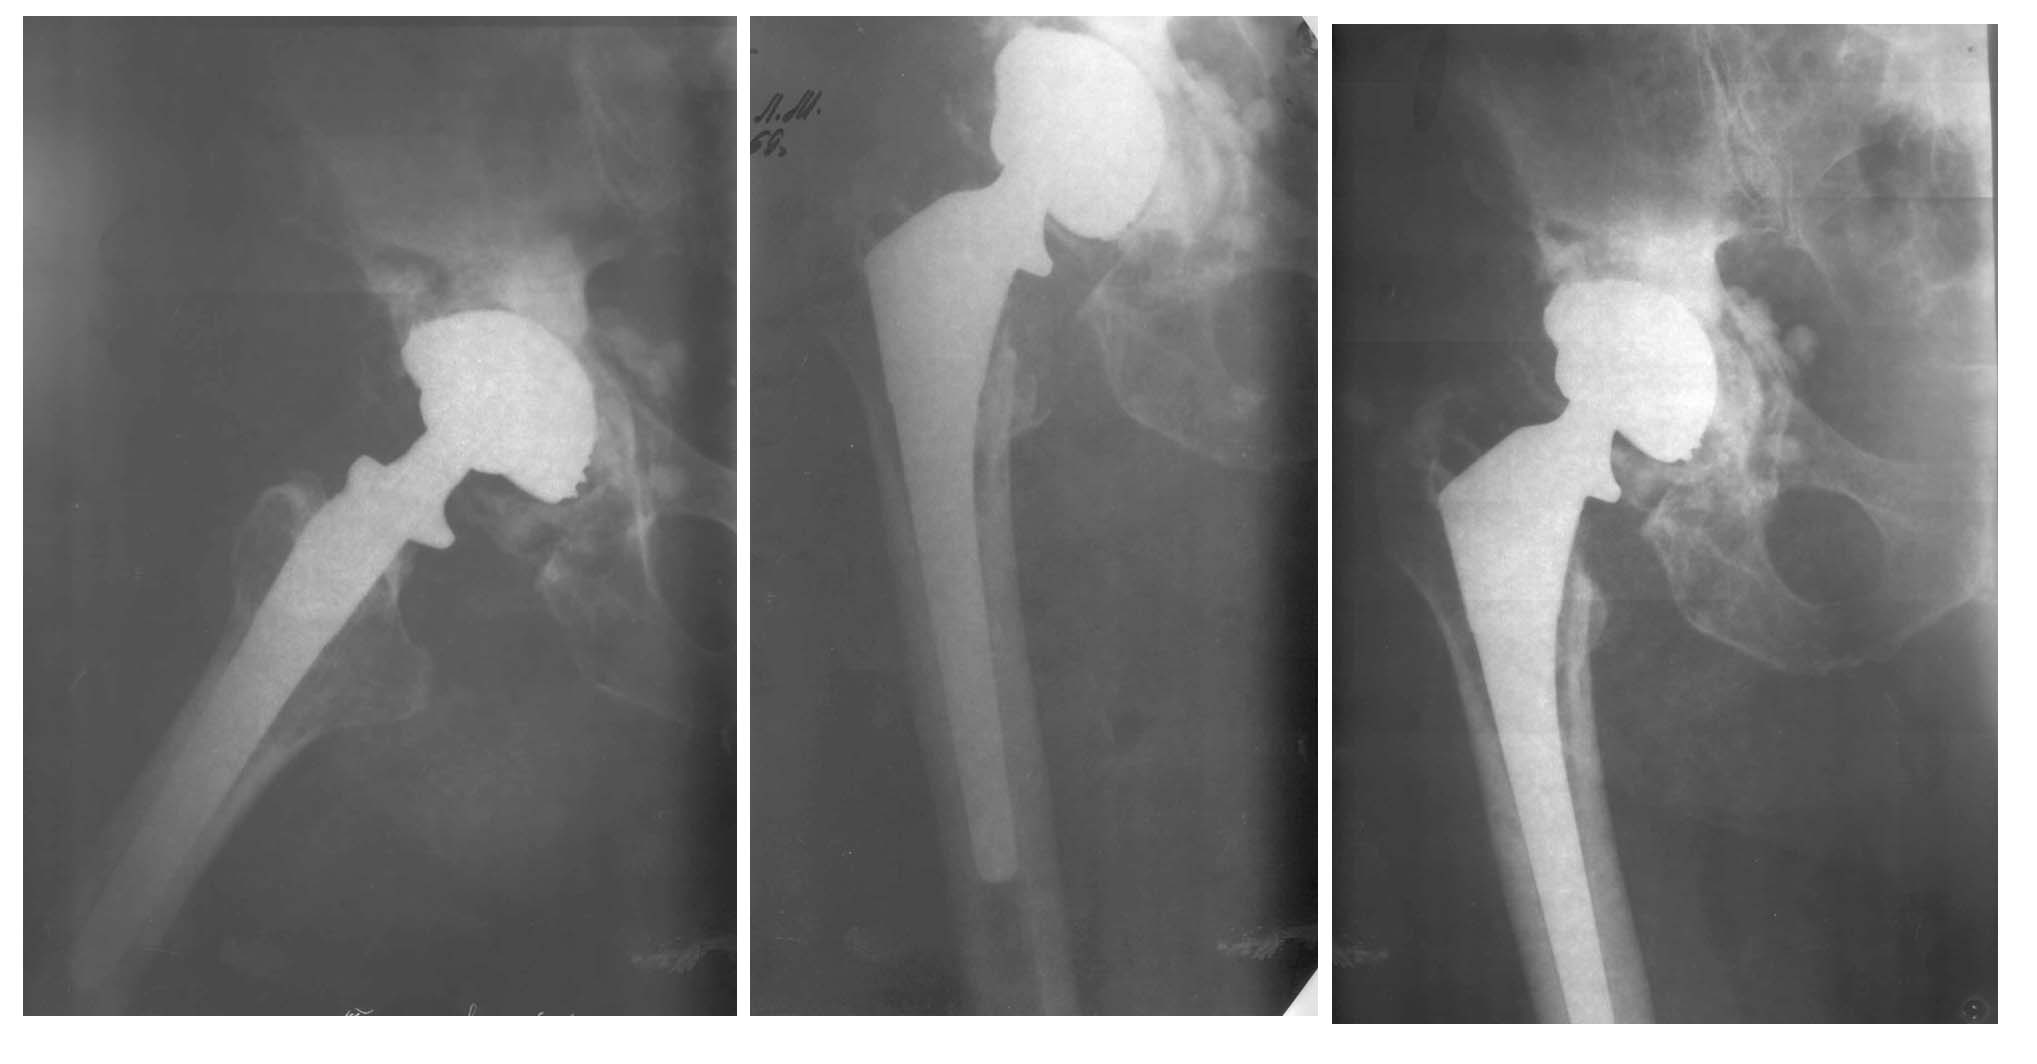

Мужчина, 70 лет. 10 лет назад прооперирован по поводу субкапитального перелома - тотальное эндопротезирование (биомед). В настоящее время жалобы на боль.Вопрос: тактика лечения?С уважением,А.В.Владзимирский

В данном случае, по рентгенографическим данным, имеет место нестабильность ацетабулярного компонента, что требует его ревизионного эндопротезирования:

Удаление чашки, костная пластика, укрепляющее кольцо, полиэтиленовый компонент на костном цементе. замена головки.

Мне кажется, что бедренный компонент стабилен.

Рентгенограммы не очень чёткие.

Насколько я смог разглядеть с бедренным компонентом вроде бы проблем нет.

Признаков остеоинтеграции вокруг ацетабулярного компонента не видно, создаётся впечатление, что чашка просто *болтается* в вертлужной впадине.

По всей вероятности, отсюда и боли.

Как следствие этого- ревизия ацетабулярного компонента избавила бы пациента от боли.

Случай очень знакомый. Именно Биомед и наличие болей за счет расшатывания вворачивающейся чашки. В октябре 2001 года оперировал и получил следующее: Удалил чашку и механически очистил ложе. Установил цементируемую чашку. В Вашем случае может потребоваться опорное кольцо, поскольку костная пластика затруднена в виду отсутствия головки. Ножку лучше не трогать. Она врастает очень хорошо и дедуле хватит на долго. Очень важно, что конус у БИОМЕДА отличается от стандартного (12/14) и если после замены чашки возникнет необходимость замены головки, то могут быть проблемы. АИФ